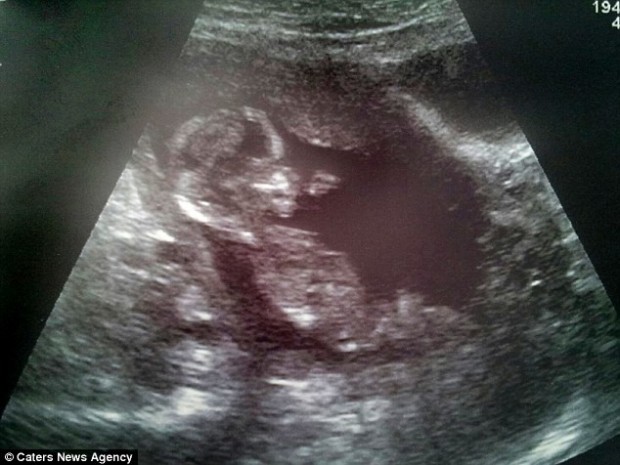

Reino Unido.- Sarah Sharples, de 25 años de edad y su esposo Lee, de 37 años de edad, se embarazaron y cuando se enteraron por los ultrasonidos que tendrían una niña, empezaron a comprar toda clase de artículos, ropa y muebles, en color rosa y con inspiración femenina.

El problema fue que al nacer la "pequeña princesa", resultó ser un varón. "Yo no podía entender cuando la partera dijo que era un niño. Todas las exploraciones confirmaron que era una niña y yo tenía todo preparado en rosa", declaró la madre.

Cuando la pareja se enteró que tendrían un hijo, quisieron saber el sexo del bebé para tener todo listo. Los médicos les dijeron que se trataba de una niña y ellos no escatimaron esfuerzos en comprar todo para su primera hija.